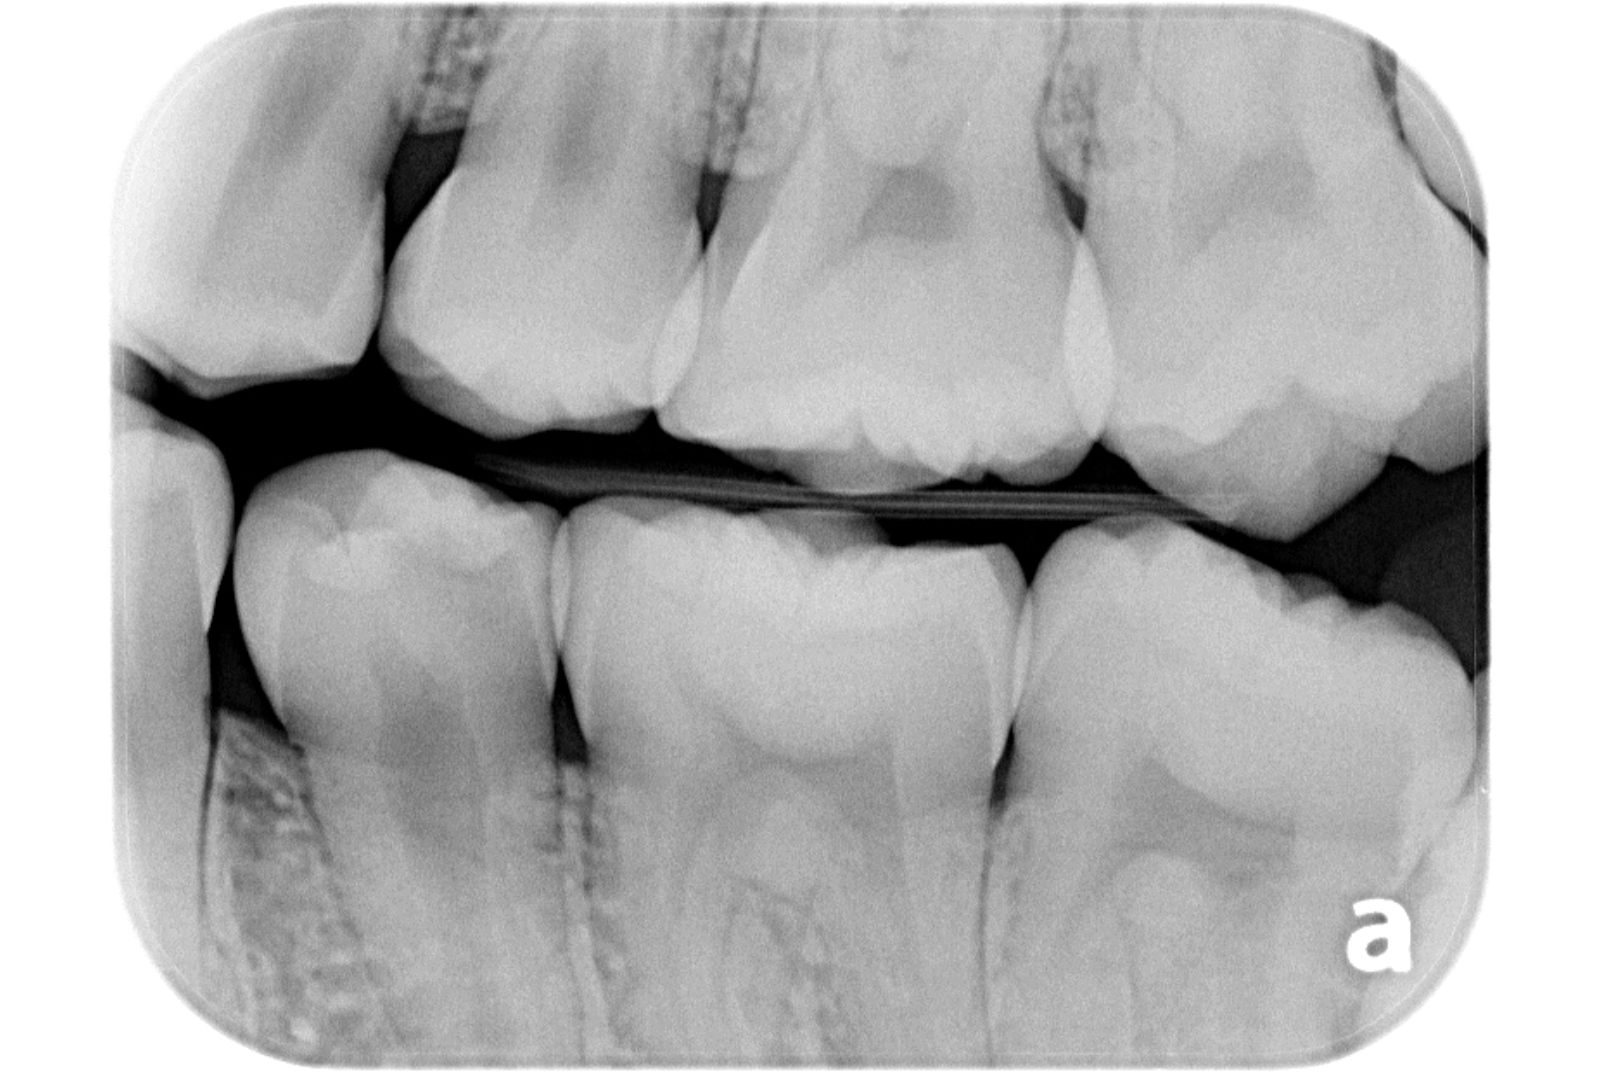

治療例 写真とレントゲン

治療前

治療後

※治療例に記載の情報はあくまでも症例に対してのものとなります。

| 費用 | 外科的歯内療法 (1年以内) 143,000円(税込) |

|---|---|

| 治療期間 | 1日 |

| 治療回数 | 1回 |

| 主な副作用とリスク | 術後に歯内退縮を起こすことがあります。 歯根破折を認めた場合、保存不可能と判断する場合があります。 |